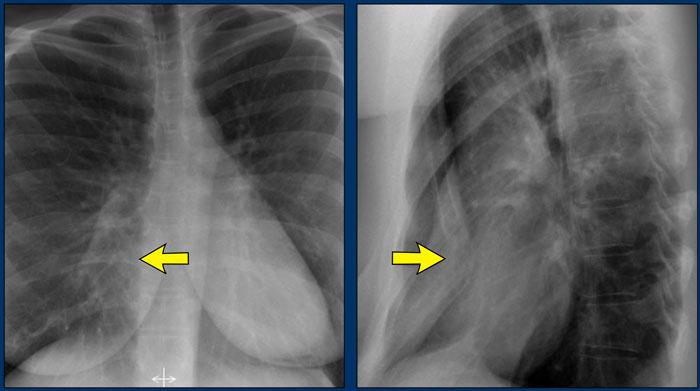

Ở bệnh nhân có lõm ngực (pectus excavatum), bờ tim phải có thể trông không rõ nét trên phim X-quang ngực thẳng.

Hình ảnh này có thể bắt chước đông đặc hoặc xẹp thùy giữa phổi phải do mất bóng mờ viền bình thường (dấu hiệu bóng mờ viền).

Phim X-quang ngực tư thế nghiêng đặc biệt hữu ích trong những trường hợp này để xác nhận chẩn đoán.

Lõm ngực là một dị tật bẩm sinh của thành ngực trước, đặc trưng bởi sự dịch chuyển ra sau của xương ức và các sụn sườn lân cận, tạo ra hình ảnh lõm của thành ngực trước.